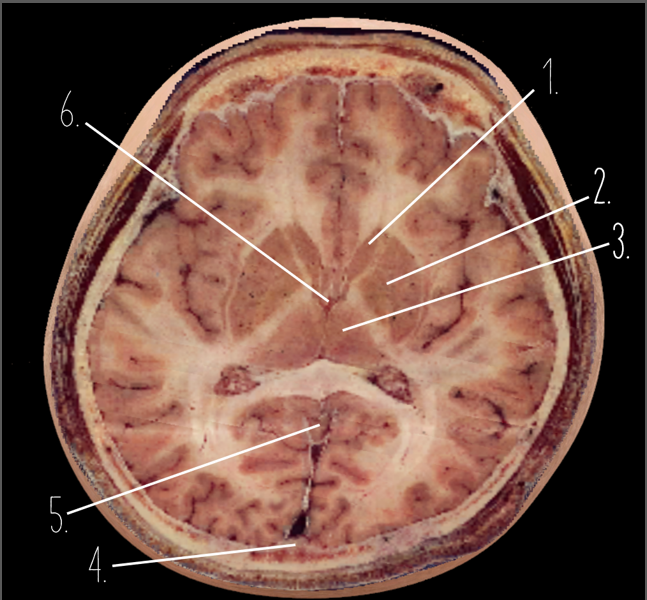

1

Frontal Bone

2

Frontal Lobe

3?

Falx Cerebri

4?

Gray Matter

5?

White Matter

6?

Sulcus